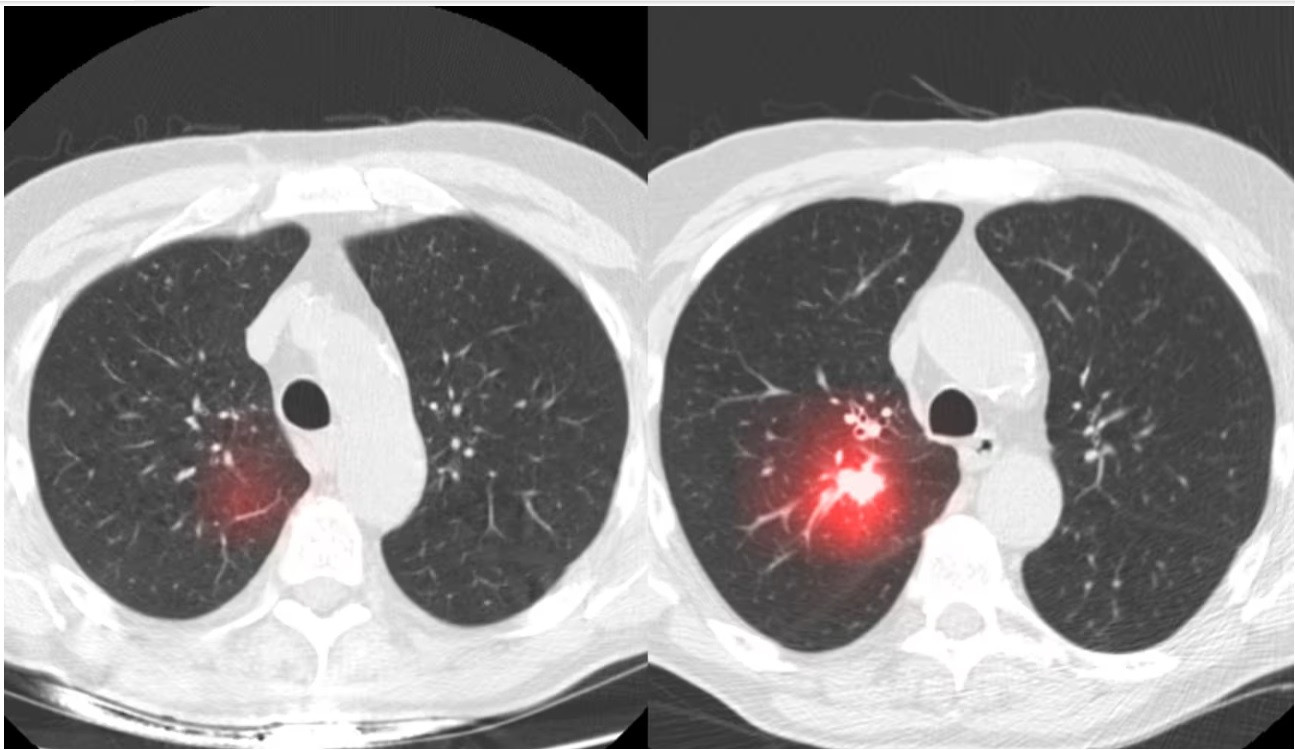

O să vorbim aplicat pe aceste tomografii. Sunt tomografii făcute la o diferență de 2 ani pentru aceeași persoană.

În prima imagine vorbim despre o tomografie pulmonară. Medicul radiolog nu a observat nimic neregulă, atunci totul era perfect sănătos. Doar că din câte vedeți aici, în zona aceasta încercuită inteligența artificială, adică Sybil, a ajuns la concluzia că cel mai probabil în următorii ani această persoană va dezvolta cancer pulmonar în acea zonă.

2 ani mai târziu, aceeași persoană, un alt computer tomograf, doar că de data aceasta veștile au fost proaste de la bun început.

În zona aceasta, exact unde a prezis Sybil, a apărut cancerul pulmonar. Este interesant ce au făcut acești cercetători și medici me la MIT din Statele Unite ale Americii. Vorbim despre Massachusetts Institute of Technology. Ei au lucrat împreună cu medicii și specialiștii din domeniul de la Harvard Medical School.